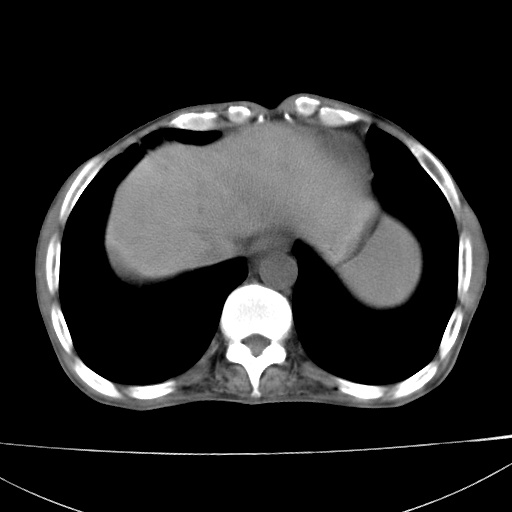

患者 男  41岁,右上腹痛伴腹泻10天,8年前有乙肝,本次b超查肝右叶占位来做ct ,请会诊!

肝硬化\\脾大\\门静脉高压,胃底静脉曲张可能性大.肝右叶肝癌肝内转移,建议增强.左侧小结石.

肝右叶肝癌肝内转移,建议增强

支持肝癌伴肝内转移,脾大,门静脉高压,胃底静脉曲张。

1)考虑肝癌;建议行ct增强扫描检查。2)脾大,门静脉高压,胃底静脉曲张。3)左肾小结石。

1)考虑肝癌及门脉瘤栓,建议行ct增强扫描检查。2)脾大,门静脉高压,胃底静脉曲张。3)左肾小结石。

结合病史;考虑肝癌。门静脉高压,脾大。胃底静脉曲张。

1)考虑肝癌;2)脾大,门静脉高压,胃底静脉曲张。3)左肾小结石。建议行ct增强扫描检查。